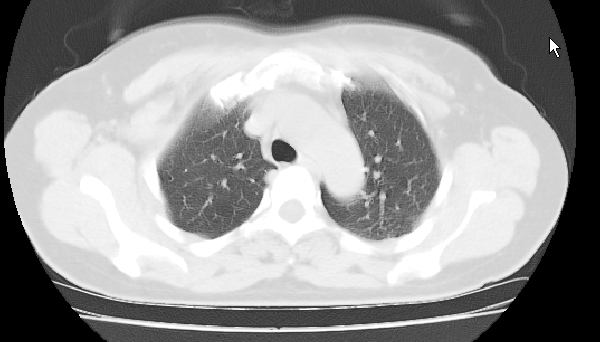

标题: CT25227:背部疼痛伴双侧胸壁痛2月,食欲差。 [打印本页]

标题: CT25227:背部疼痛伴双侧胸壁痛2月,食欲差。

肺结核并胸椎结核?请各位高手指教。

用椎体的条件来扫胸椎呀!考虑1左侧胸膜小结节形成2椎体结核并冷脓肿形成

左肺结核灶,胸椎结核并冷脓肿。

左肺结核灶,胸椎结核并冷脓肿

考虑胸椎结核并椎旁软组织肿胀。